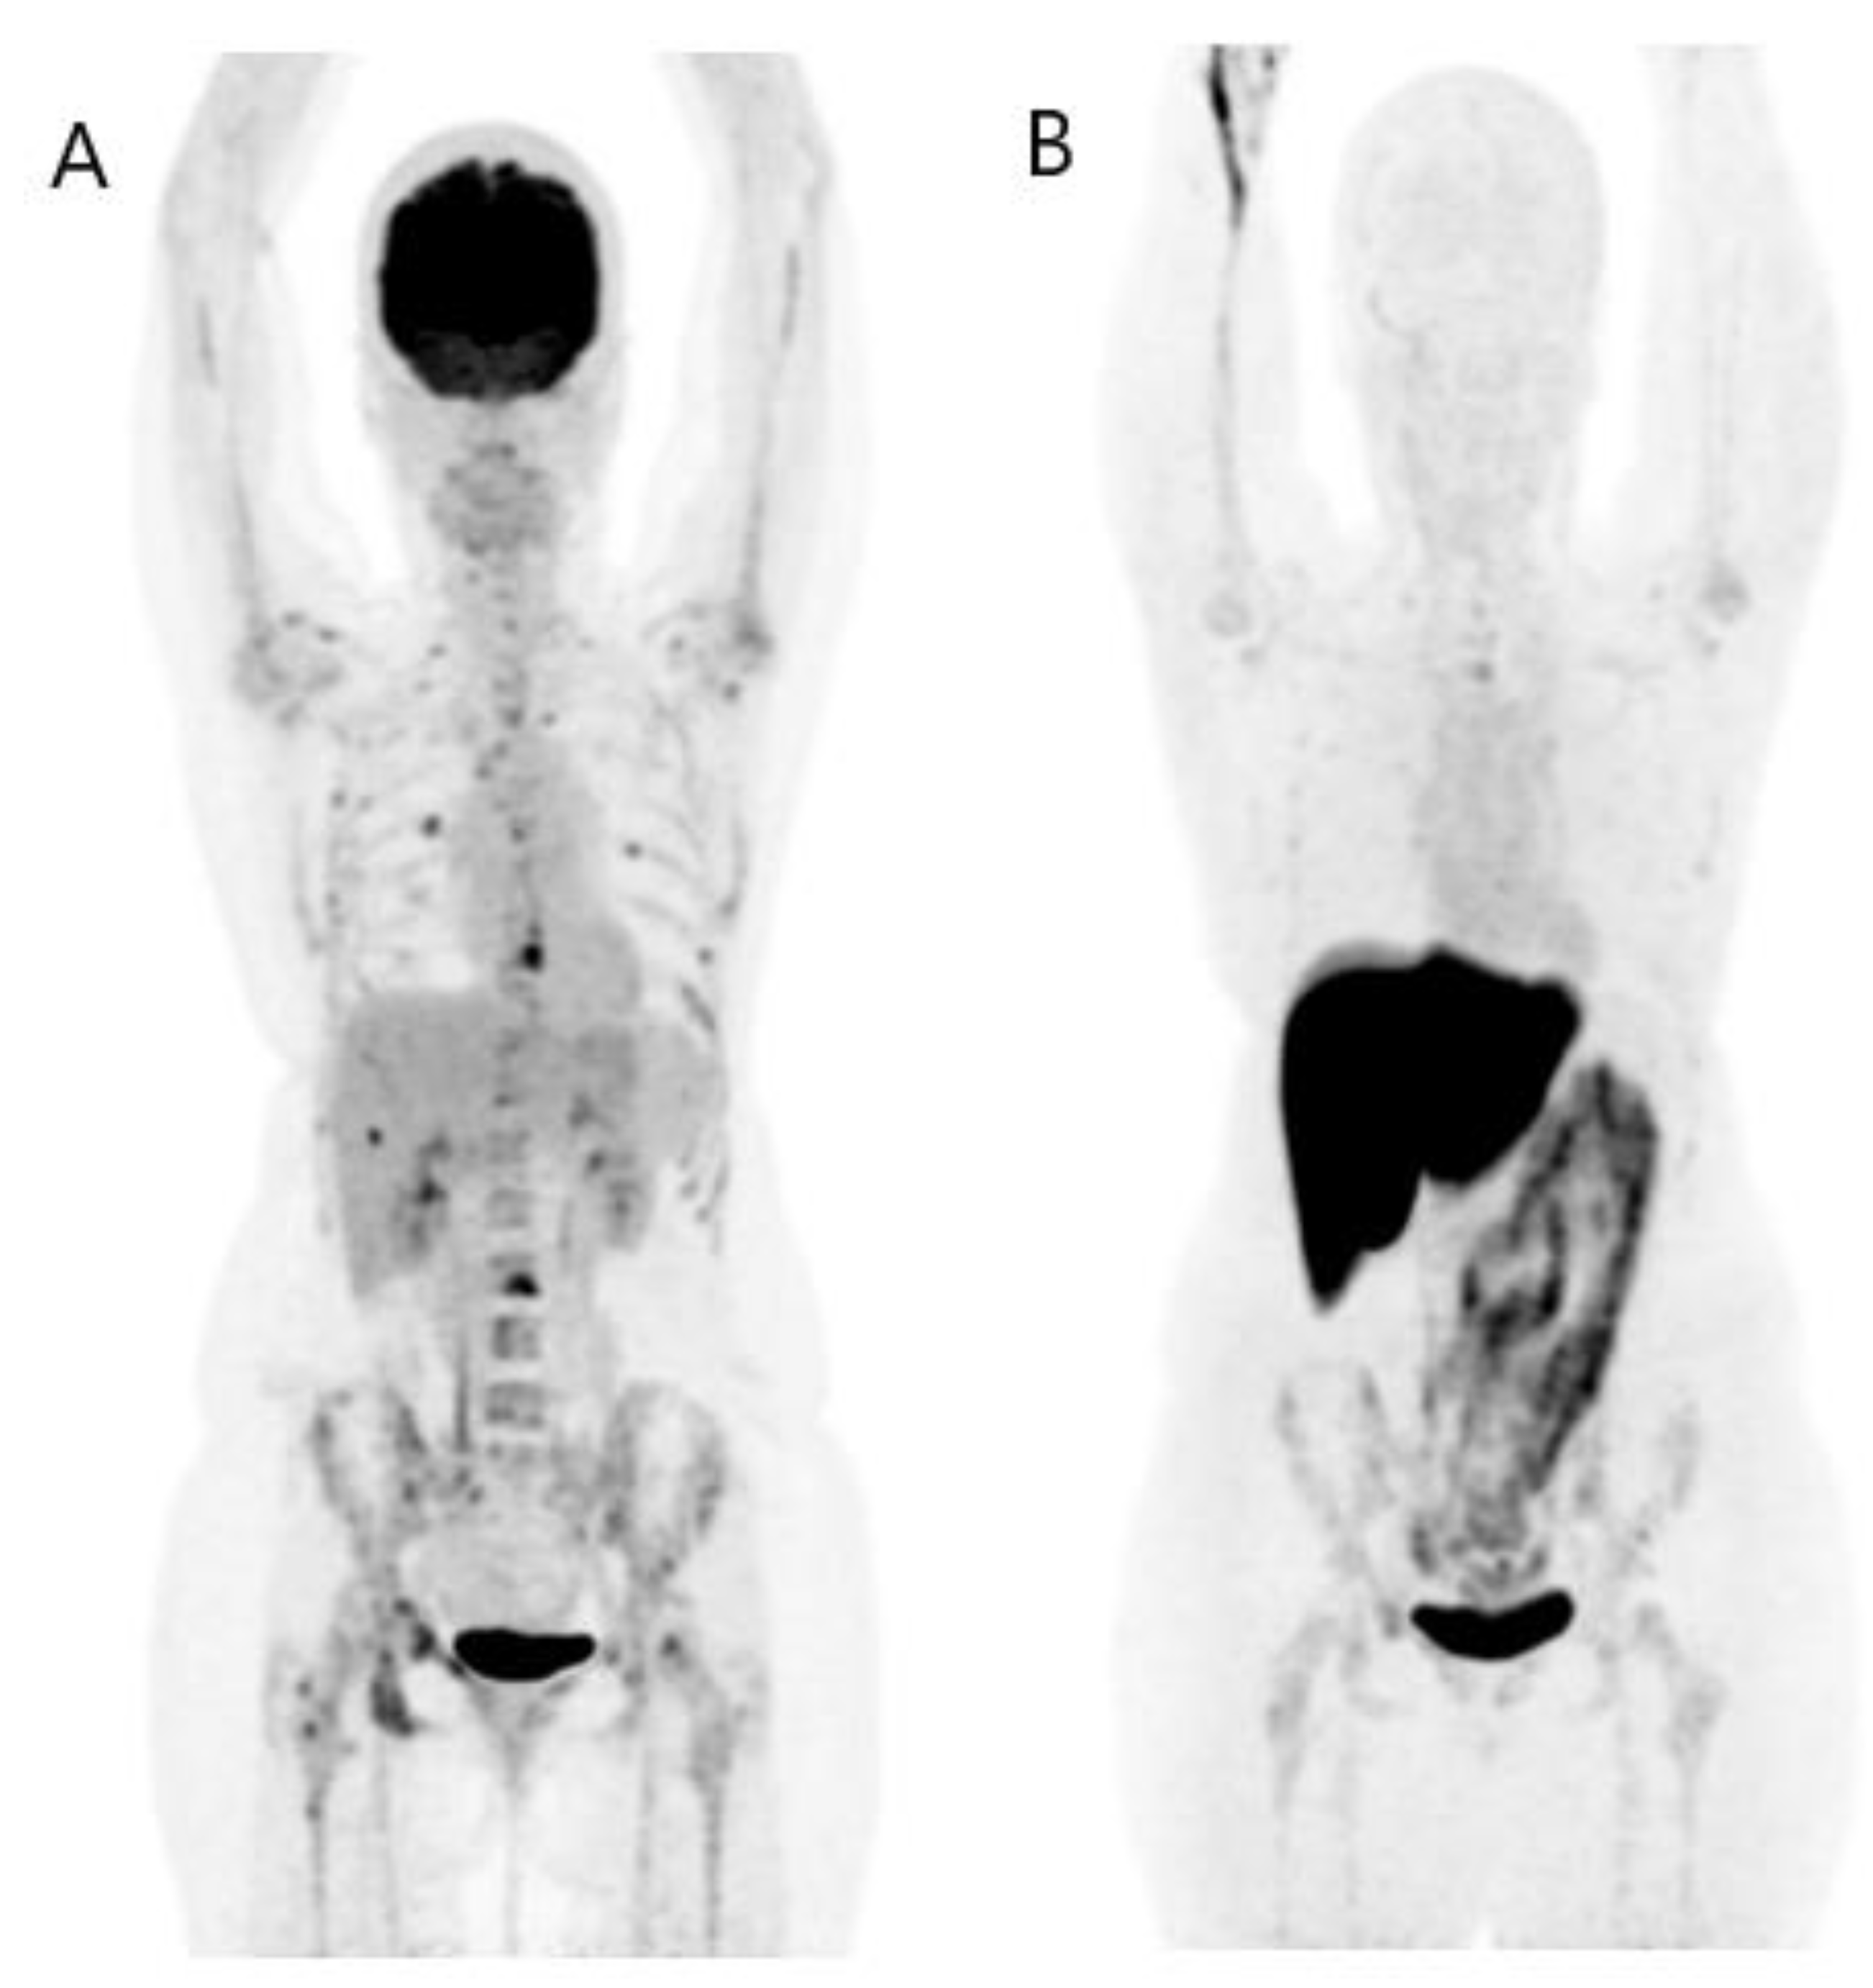

- Groheux, D.; Giacchetti, S.; Delord, M.; Hindié, E.; Vercellino, L.; Cuvier, C.; Toubert, M.E.; Merlet, P.; Hennequin, C.; Espié, M. 18F-FDG PET/CT in staging patients with locally advanced or inflammatory breast cancer: Comparison to conventional staging. J. Nucl. Med. 2013, 54, 5–11. [Google Scholar] [CrossRef]

- Fuster, D.; Duch, J.; Paredes, P.; Velasco, M.; Muñoz, M.; Santamaría, G.; Fontanillas, M.; Pons, F. Preoperative staging of large primary breast cancer with [18F]fluorodeoxyglucose positron emission tomography/computed tomography compared with conventional imaging procedures. J. Clin. Oncol. 2008, 26, 4746–4751. [Google Scholar] [CrossRef] [PubMed]

- Vogsen, M.; Jensen, J.D.; Christensen, I.Y.; Gerke, O.; Jylling, A.M.B.; Larsen, L.B.; Braad, P.E.; Søe, K.L.; Bille, C.; Ewertz, M. FDG-PET/CT in high-risk primary breast cancer-a prospective study of stage migration and clinical impact. Breast Cancer Res. Treat. 2021, 185, 145–153. [Google Scholar] [CrossRef]

- Groheux, D.; Moretti, J.L.; Baillet, G.; Espie, M.; Giacchetti, S.; Hindie, E.; Hennequin, C.; Vilcoq, J.R.; Cuvier, C.; Toubert, M.E. Effect of (18)F-FDG PET/CT imaging in patients with clinical Stage II and III breast cancer. Int. J. Radiat. Oncol. Biol. Phys. 2008, 71, 695–704. [Google Scholar] [PubMed]